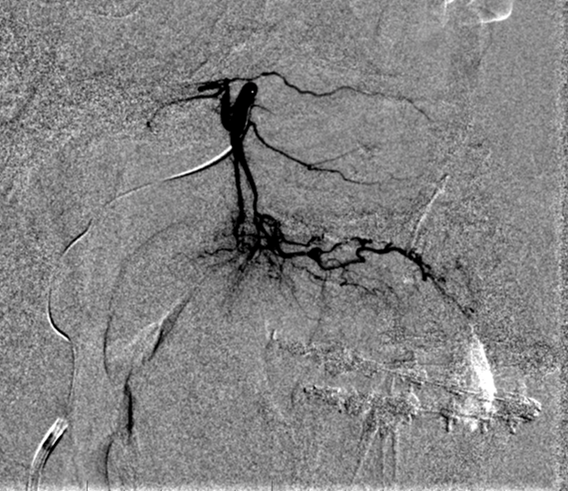

Se realiza artreiografia diagnostica que demuestra un pseudoaneurisma de 23 mm de la arteria palatina mayor descendente derecha a nivel del paladar duro- suelo del seno maxilar derecho en relación a la zona de osteosíntesis.

A nivel de la ACE izda se aprecia otro seudoaneurisma de 40 mm que se insínua en el interior del seno maxilar izquierdo desde la arteria palatina mayor descendente izquierda. No se aprecian otras alteraciones valorables en las arterias estudiadas.

Informe: Se cateteriza la arteria maxilar interna izquierda confirmando la persistencia del

pseudoaneurisma de arteria palatina mayor descendente izquierda la cual se logra microcateterizar con

Marathon 1.5F. Proximal al pseudoaneurisma se inyecta 1 cc de Glubrán al 50% logrando un relleno

completo del mismo y de un corto segmento proximal de la arteria. No se observan complicaciones durante

el procedimiento